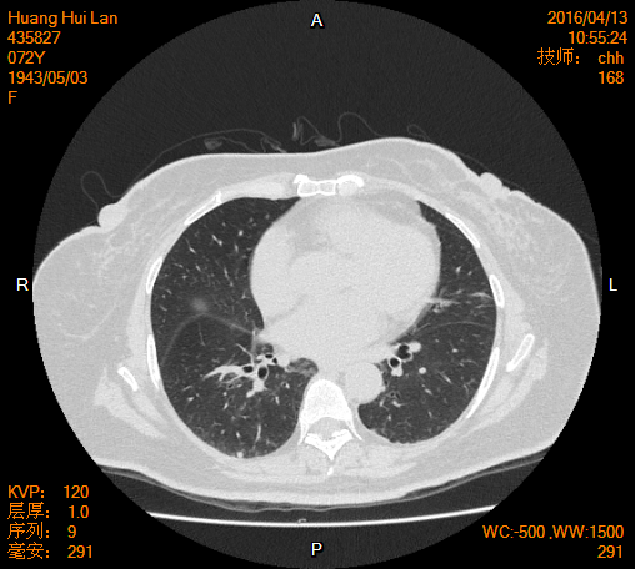

2016-04-13胸腹盆CT

左侧附件区肿块,代谢活跃,考虑卵巢囊腺癌;直肠壁增厚,代谢活跃,考虑直肠癌并周围淋巴结转移可能性大,建议肠镜检查;双肺多发结节,考虑转移瘤;腹腔积液